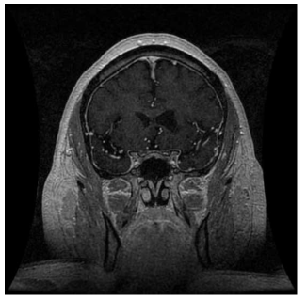

Figure 2: Post-contrast T1-weighted MRI image demonstrating leftventricular dilatation due to atrophy, suggestive of past basal ganglia stroke.